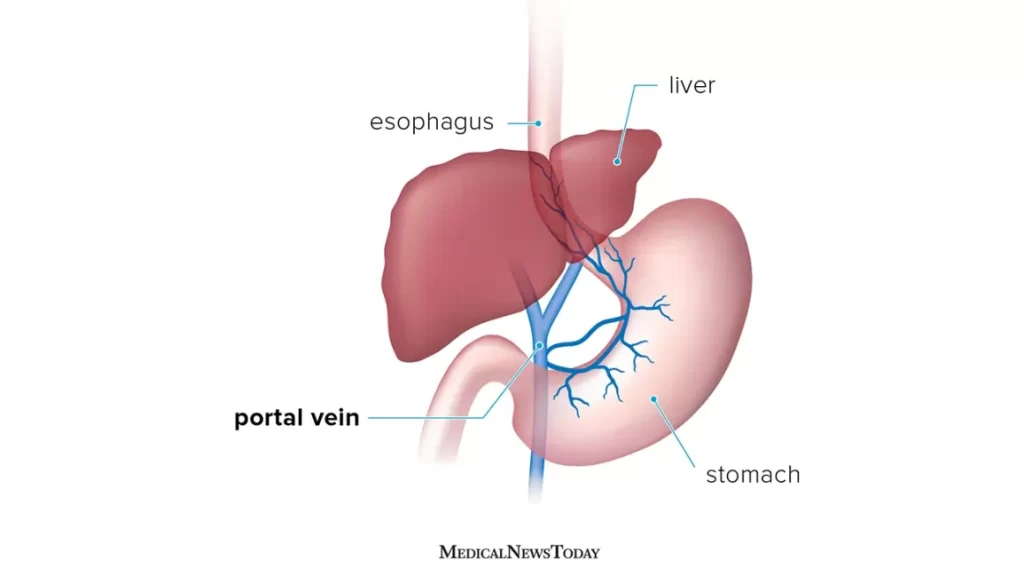

Portal Hypertension Management

"Effectively managing portal hypertension is vital for individuals with increased portal vein pressure, often associated with liver cirrhosis. Strategies include medications like beta-blockers to lower pressure and prevent variceal bleeding, endoscopic procedures such as band ligation to address esophageal varices, and, in severe cases, Transjugular Intrahepatic Portosystemic Shunt (TIPS) for redirecting blood flow. Ascites is managed with diuretics and, when necessary, paracentesis. Regular monitoring and, if appropriate, liver transplantation contribute to comprehensive portal hypertension care